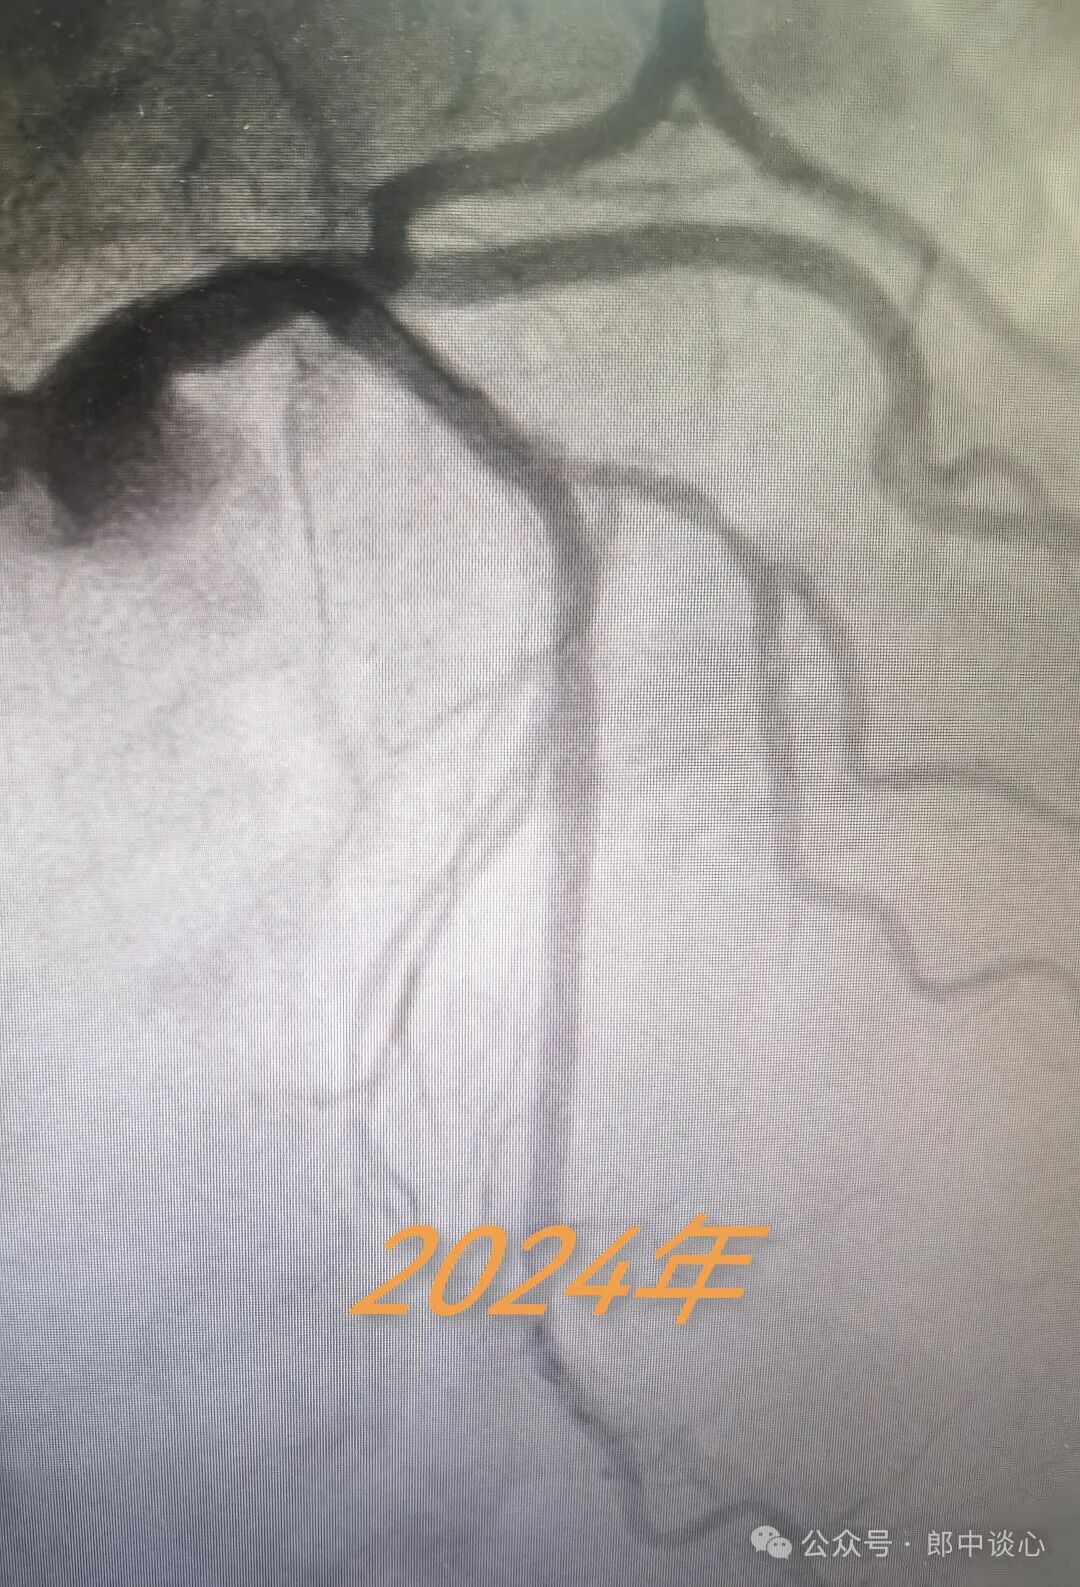

又过去了一个6年,2024年他又心绞痛了!

再做造影,六年前PTCA的对角支保持得还不错,{1}部位似乎还是六年前的那个临界病变,但前降支{2}部位出现了一个“新”的病变!

难道{2}就是他本次的犯罪病变?或者说他本次缺血心绞痛发作是与{1}病变的叠加效应?

假定是这样,是不是这次只需要处理病变{2}就可以了?继续不动病变{1}?